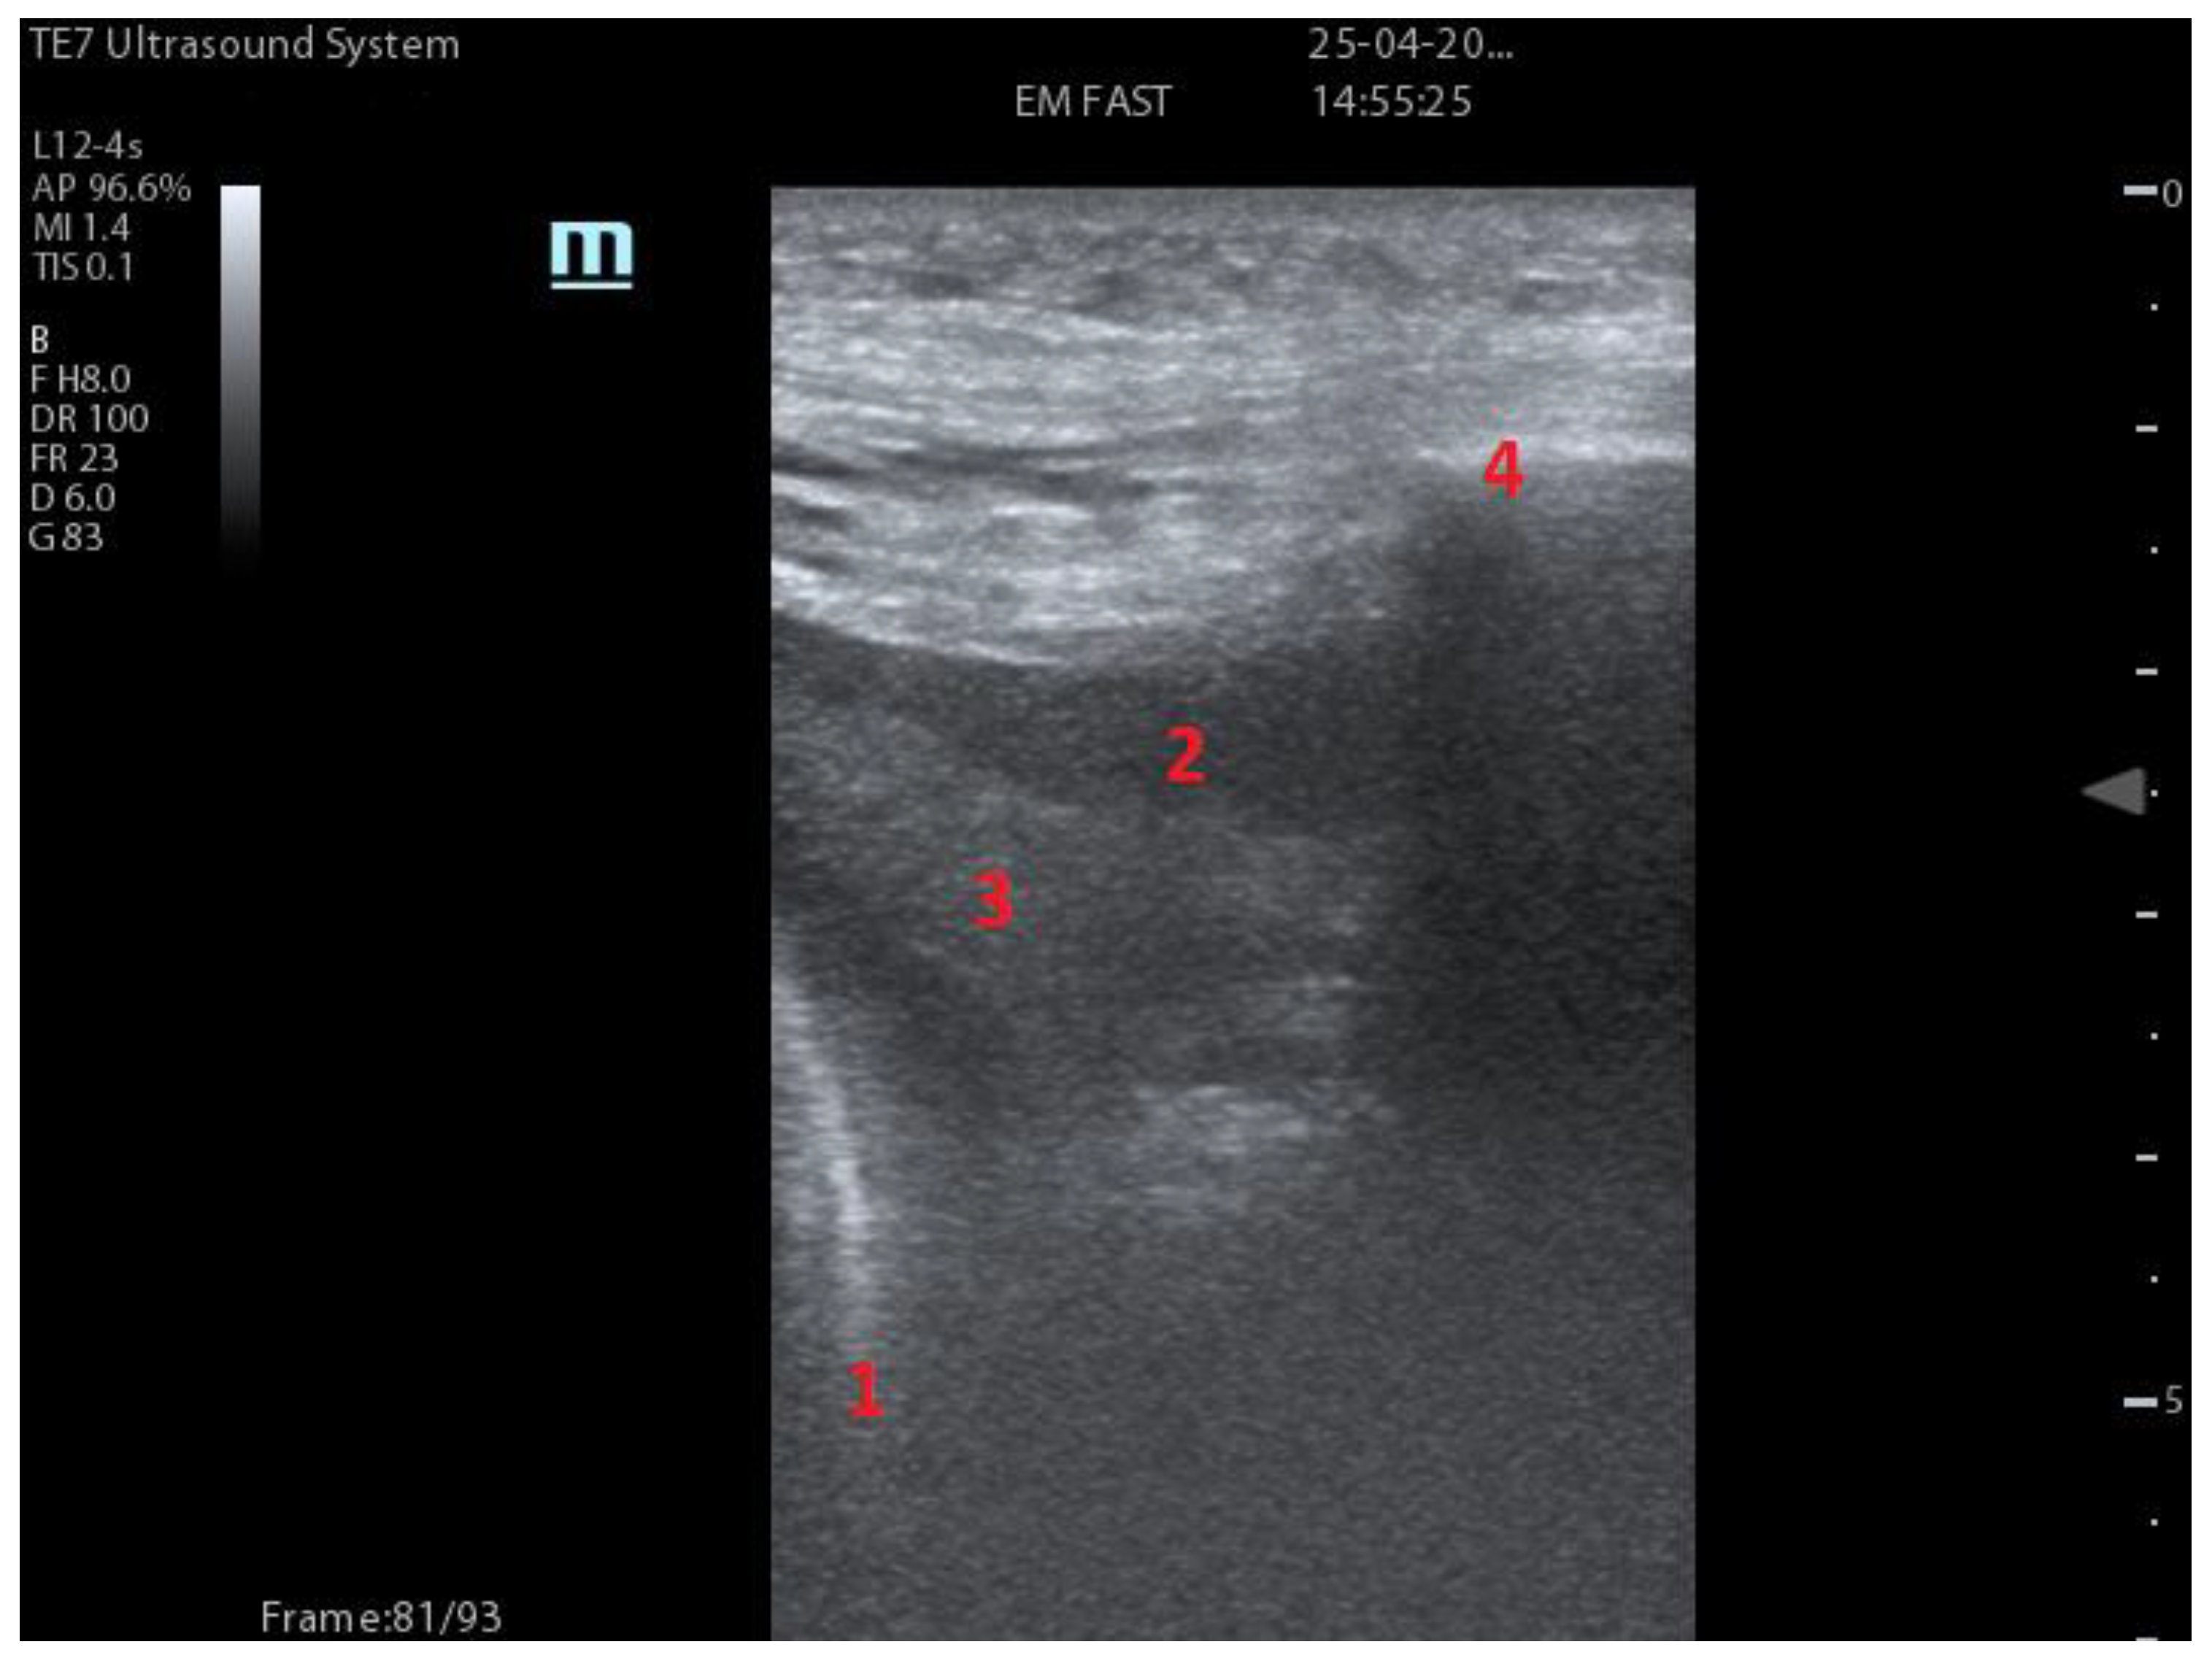

| Integrated ultrasound score (I-LUS) [41] | 0: A-lines or ≤2 B-lines plus regular sliding 1: ≥3 B lines or spaced focal points plus regular sliding 2: coalescing B-lines 3: pulmonary consolidations Plus: Presence of pleural effusion (1: present, 0: absent). Presence of pericardial effusion (1: present, 0: absent). Measurement of the IVC respiratory variation (<0–33%) (1: present, 0: absent). Diaphragm excursion: measured in normal respiration, with M-mode through a right subcostal scan. A value > 2 +/− 0.5 cm is considered normal (0 points), while an inferior value is considered abnormal (1 point). | ![]() 12 AREAS |